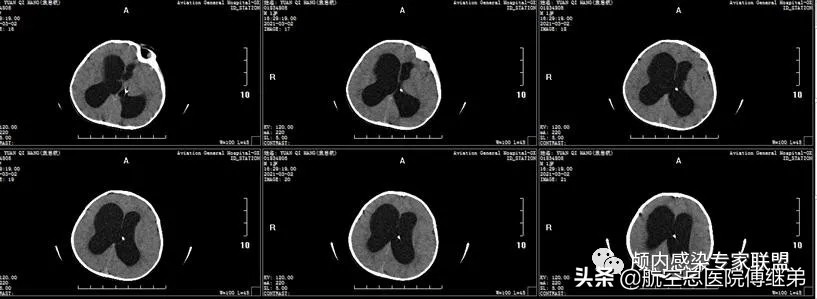

患儿于2021-03-02入院,入院时烦躁,瞳孔及肢体活动尚可,骨窗膨出,呕吐。查脑脊液检查可见:白细胞 389.0*10^6/L 单个核细胞 38% 多核细胞 62.0% 葡萄糖 0.37mmol/L。入院时复查颅脑CT可见储液囊(ommaya囊)存在,脑室系统仍扩张(图三/四)。

图三 脑室系统扩张,皮下储液囊植入

图四 脑室系统扩张,皮下储液囊植入